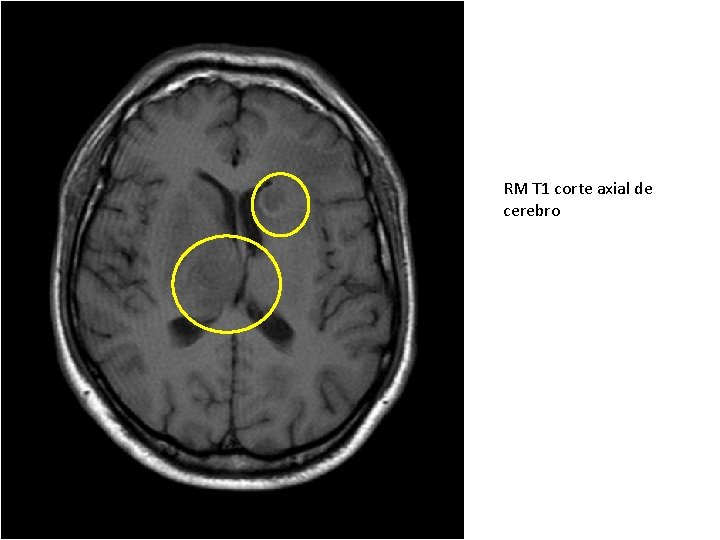

RM T 1 corte axial de cerebro

RM T 1 COM CONTRASTE Lesão anelar da neurotoxo não tem capsula